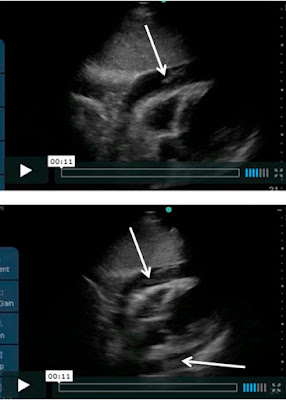

Стандартная эхокардиограмма:

- Регионарное нарушение движения стенки - боковой и нижнебоковой сегменты